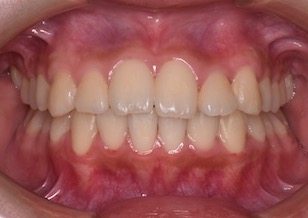

早期治療による永久歯のためのスペース不足の軽減治療と成長発育の旺盛な時期にヘッドギアによる上顎骨の成長コントロール(抑制)治療の効果が十分あらわれ、その後の再診断により、小臼歯非抜歯にて上下顎歯列はキレイに整い、すべてのエリアで正常で機能的な咬み合わせを得ることができました。

After Ⅳの写真は、治療後の口腔内写真です。